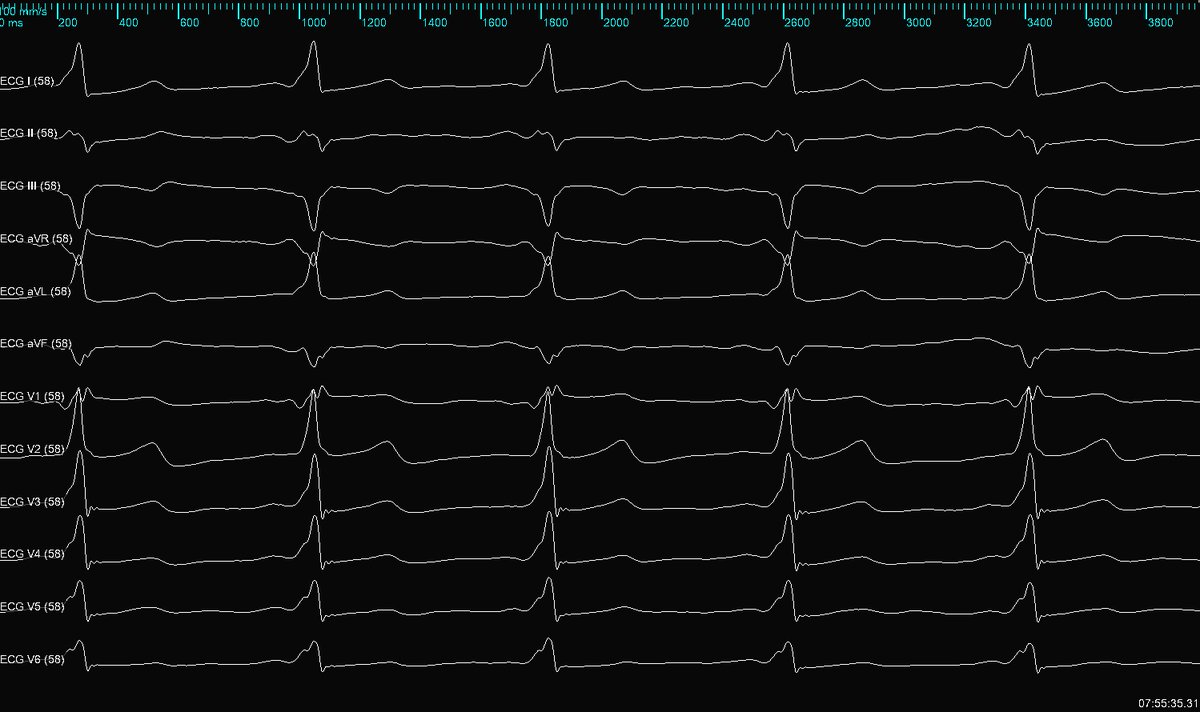

PLSVC is common; PLSVC w/o right SVC (isolated SVC) and a GIANT coronary sinus isn’t. This aneurysmal CS is like another cardiac chamber. Flutter termination in a patient with history of CABG. #mapmoreburnless #EPeeps #HDGrid #atypicalflutter #JustATypicalDayinEP @ArHeartHospital

MonicaYLo's tweet image. PLSVC is common; PLSVC w/o right SVC (isolated SVC) and a GIANT coronary sinus isn’t. This aneurysmal CS is like another cardiac chamber. Flutter termination in a patient with history of CABG. #mapmoreburnless #EPeeps #HDGrid #atypicalflutter #JustATypicalDayinEP @ArHeartHospital